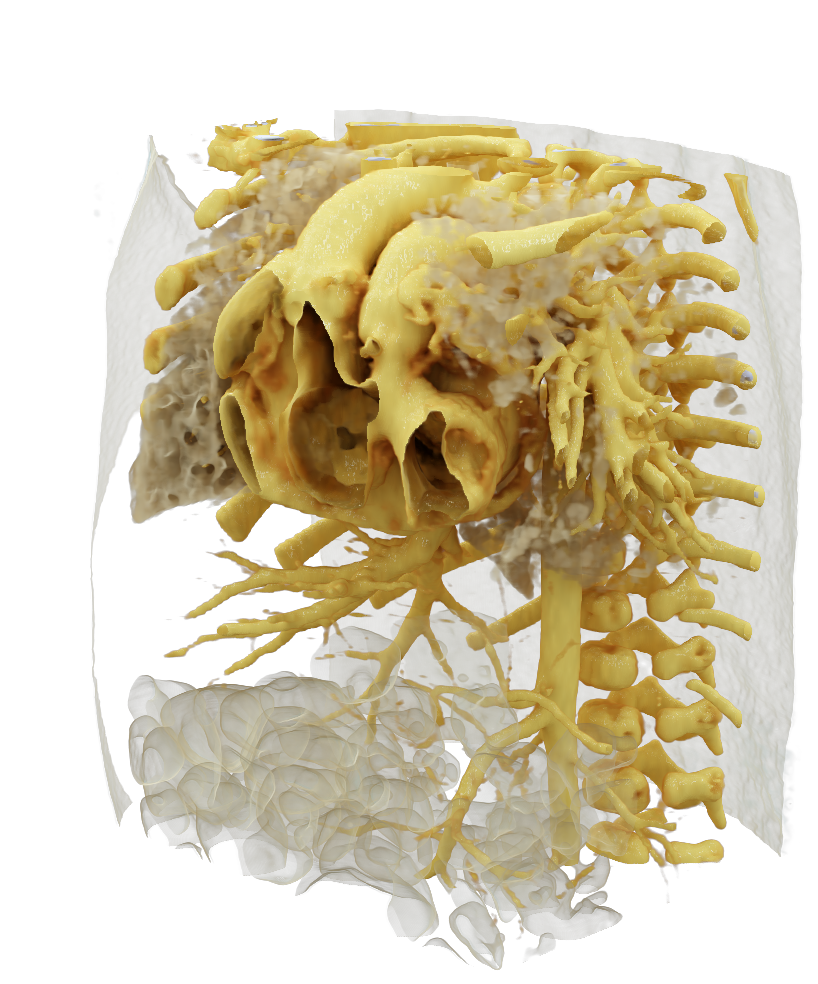

Visualize the smallest structures of the heart realistically without surgery? About the use of a prototype that makes this vision almost tangible.

Cardiac surgery is one of the most difficult procedures, and it gets even more complex when it comes to operating on tiny children’s hearts. Visualization techniques like cinematic rendering provide a detailed 3-D view of the patient’s heart and surrounding anatomy. But what happens when these images are turned into a hologram that can be rotated, zoomed, and looked at from all possible perspectives?